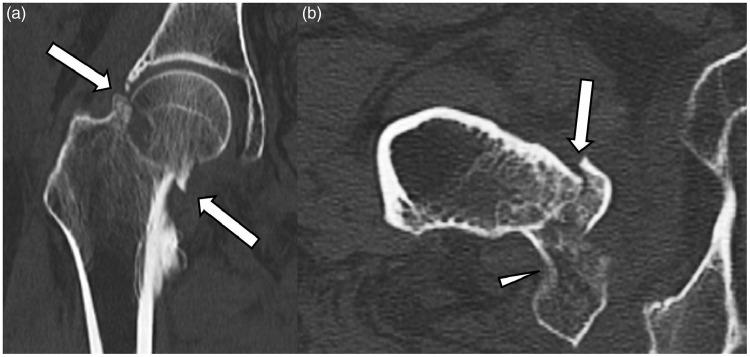

We present the case of a 53-year-old woman with a known history of hereditary multiple exostosis disease referred for further imaging work-up after ultrasound and computed tomography leading to the suspicion of malignant transformation of an osteochondroma (exostosis) located on the posteromedial aspect of the right proximal femur. Imaging examinations suggested an ischiofemoral impingement resulting in a secondary bursitis associated with the development of an internal lipoma arborescens. This rare association explained the complexity of the diagnosis. Magnetic resonance imaging (MRI) played a key role in correctly identifying this benign complication of the osteochondroma and in distinguishing those observations from a secondary exostotic chondrosarcoma. MRI findings were subsequently confirmed at surgery and pathological examination.

我们报告了一例53岁女性病例,该患者有遗传性多发性骨软骨瘤病病史。在超声和计算机断层扫描后,怀疑位于右股骨近端后内侧的骨软骨瘤(外生骨疣)发生恶变,遂进行进一步影像学检查。影像学检查提示坐骨股骨撞击,导致继发性滑囊炎,并伴有内部树状脂肪瘤的形成。这种罕见的关联解释了诊断的复杂性。磁共振成像(MRI)在正确识别骨软骨瘤的这种良性并发症以及将这些表现与继发性外生骨疣性软骨肉瘤区分开来方面发挥了关键作用。MRI结果随后在手术和病理检查中得到证实。